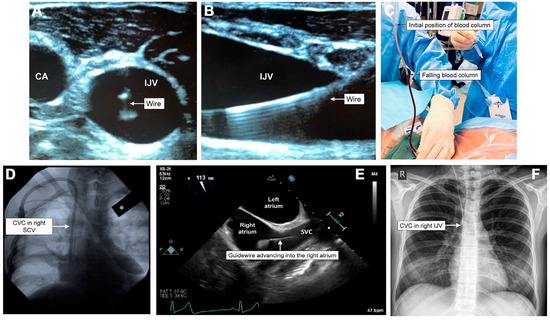

Central Venous Access: An Update on Modern Techniques to Avoid Complications

by Kai Woodfall and André van Zundert

Healthcare 2025, 13(10), 1168; https://doi.org/10.3390/healthcare13101168 - 16 May 2025

Background: Central venous catheterization (CVC) is a frequently performed procedure in anesthesia and critical care settings. Modern procedures have improved significantly, particularly with increasingly sophisticated venous verification methods and ultrasound guidance. While the associated historical complication rates reflect this improvement, complications such [...] Read more.

Background: Central venous catheterization (CVC) is a frequently performed procedure in anesthesia and critical care settings. Modern procedures have improved significantly, particularly with increasingly sophisticated venous verification methods and ultrasound guidance. While the associated historical complication rates reflect this improvement, complications such as inadvertent arterial puncture, arterial cannulation, pneumothorax, deep vein thrombosis, and catheter-associated infection are still significant risks. Methods: This narrative review was constructed from a literature review using a search strategy of the MESH terms central venous access, central venous line, complications, insertion, and puncture, published between 2015 and 2025. Inclusion criteria included peer-reviewed full-text articles. Supplementary articles were included to construct the historical perspectives on central venous access and complications. Results: Our review offers a simple management algorithm for the mechanical complications of CVC insertion. This algorithm focuses on inadvertent arterial puncture/cannulation, with steps ranging from external compression to endovascular repair or surgical intervention. Conclusions: Moving forward, clinicians are encouraged to look into the future to predict what complications may arise as our modern patient cohort evolves. When complications develop, clinicians should know how to manage them to prevent further patient morbidity. Full article

Show Figures

Figure 1